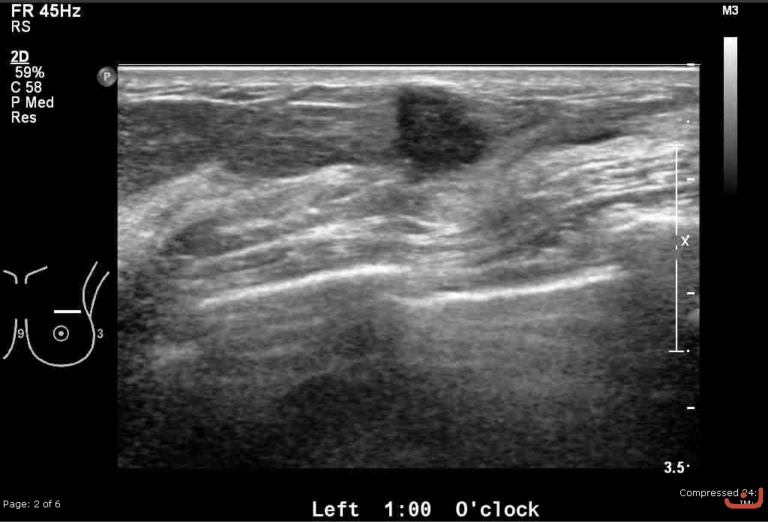

Malignant solid mass

Date

Thursday, 30 April 2015